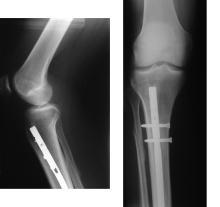

内固定:以手术的方式将金属骨钉钉合在骨折部。

外固定:从体外固定骨折部